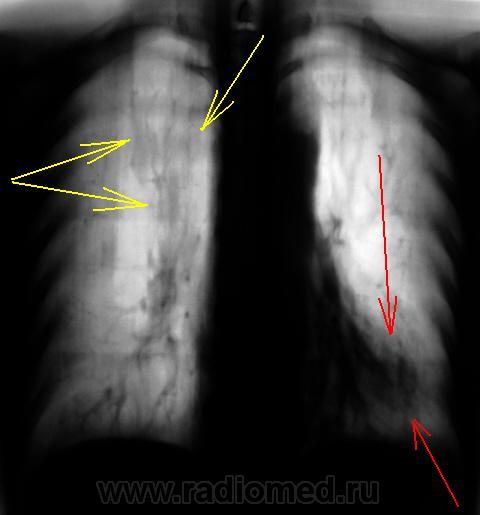

Перво-наперво смущает снижение прозрачности, помеченностое желтыми и красными стрелками - срез 7 см.

Желтые стрелки - могу предложить усиление за счет полнокровия, расширения веток ЛА, красные тянут на шварту. Клиники никакой? Анамнез (перенесенный туберкулез, травма, плеврит). Если без клинических проявлений, то вероятно, последствия перенесенного воспалительного заболевания.